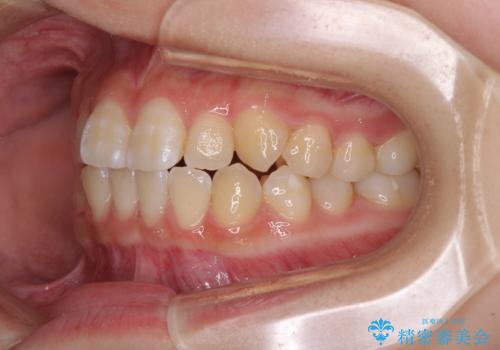

- 前歯のデコボコと磨きにくい奥歯を気にして来院された患者様です。

左右ともに上顎第二大臼歯が外側に転位しており、大変磨きにくくなっているため、補助装置により内側に引き込むことで改善することとしました。

外側を向いていた奥歯は比較的早い時期に歯列に収まり、咬み合わせも磨きやすさも改善することができました。

歯列は元々悪くなかったので、1年ほどで治療を終えることができました。